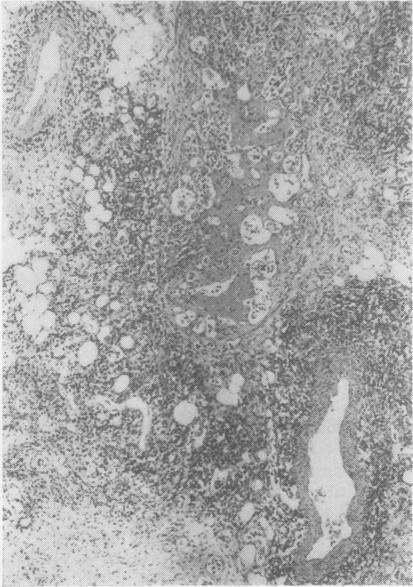

The clinical and pathological findings of a case of systemic angioendotheliomatosis are presented. The previously published cases of this disease are analysed. The present case is only the third to show clear evidence of metastasis.

本文报告了一例系统性血管内皮瘤病的临床及病理表现。对该疾病既往已发表的病例进行了分析。本病例是第三例有明确转移证据的病例。